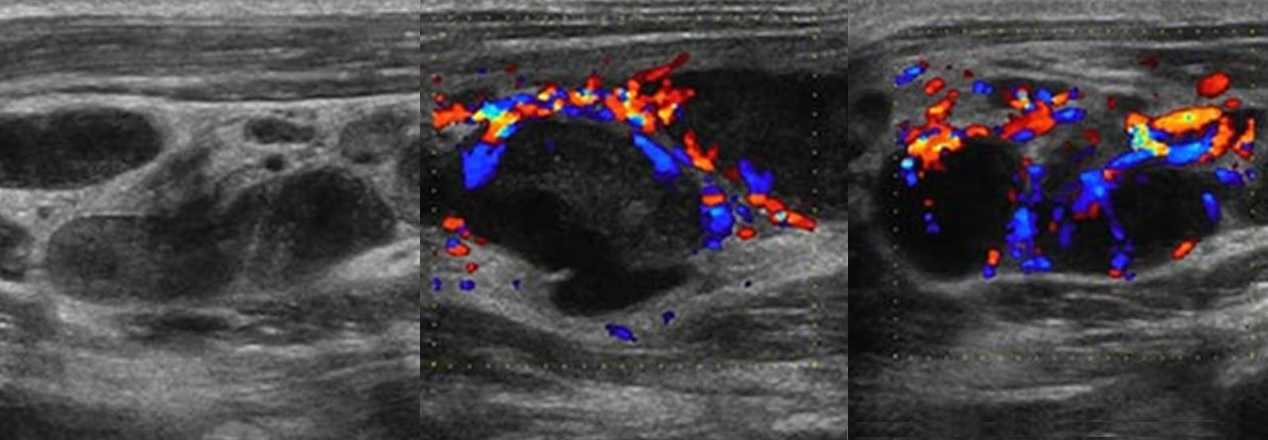

Туберкулез чаще поражает лимфоузлы шеи, подмышечной и паховой области. Обычно туберкулезный лимфаденит развивается медленно, лимфоузлы безболезненные, средний размер 3 см, но иногда могут достигать 10 см. На УЗИ пораженные лимфоузлы увеличены, гипоэхогенные, с нечетким контуром, часто можно увидеть выраженный периаденит и спаянные пакеты лимфоузлов. Для туберкулезного лимфаденита характерна неоднородная эхоструктура — анэхогенные кистозные полости и кальцинаты. При прогрессировании заболевания может образоваться абсцесс и свищи.

Рисунок. На УЗИ на шее определяется группа увеличенных лимфоузлов, неправильной формы; эхогенность понижена, центральный рубчик отсутствует; неоднородные за счет анэхогенных аваскулярных зон — очаги некроза; кровоток усилен, ход сосудов неправильный, выраженный подкапсульный кровоток. Заключение по результатам биопсии: Туберкулез лимфоузлов.

Рисунок. На УЗИ увеличенные лимфоузлы, неправильной формы с размытыми границами; эхогенность пониженная, центральный рубчик отсутствует; неоднородные за счет мелких кистозных полостей и гиперэхогенных включений с акустической тенью позади (кальцинаты). Заключение по результатам биопсии: Поражение лимфоузлов атипичными микобактериями. Гистологически очаги инфекции М. tuberculosis и атипичных микобактерий часто неразличимы. Классическим морфологическим проявлением в обоих случаях служит гранулема с казеозным некрозом.